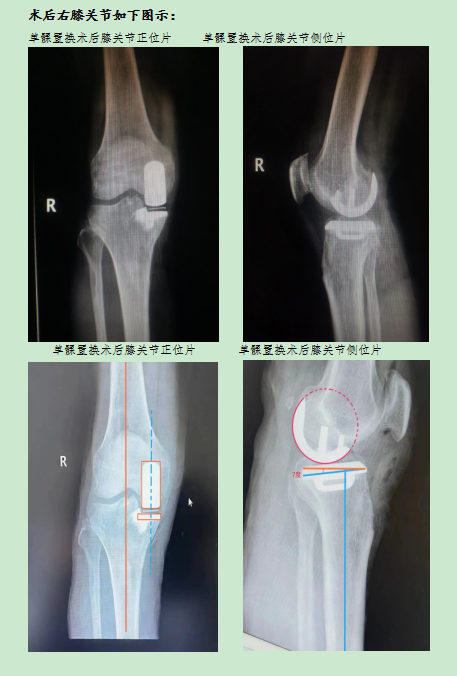

該患者入院后,完善相關(guān)檢查,蔡成成主任和主管醫(yī)生對(duì)患者全面評(píng)估后,制定出最佳的治療方案,鑒于患者右膝關(guān)節(jié)畸形尚不嚴(yán)重,活動(dòng)度尚可,計(jì)劃先行“左側(cè)全膝關(guān)節(jié)置換術(shù)”,待左膝關(guān)節(jié)傷口愈合、功能恢復(fù)后,再行“右側(cè)膝關(guān)節(jié)單髁置換術(shù)”,在醫(yī)護(hù)人員精心治療護(hù)理下,在患者及家屬配合下,順利為患者先后完成兩次手術(shù)治療。術(shù)后患者切口愈合良好,雙側(cè)膝關(guān)節(jié)屈伸活動(dòng)良好,兩次手術(shù)均在術(shù)后第二天下床活動(dòng),經(jīng)過(guò)為期三周的規(guī)范治療與功能鍛煉,該患者康復(fù)出院,出院時(shí)已擺脫輪椅自行下樓,完全恢復(fù)正常行動(dòng)。這是我科獨(dú)立成功完成的首例“人工膝關(guān)節(jié)單髁置換術(shù)”,標(biāo)志著我院骨科在關(guān)節(jié)置換領(lǐng)域向微創(chuàng)化、精準(zhǔn)化方向再次邁進(jìn)一步。

與全膝置換術(shù)相比,膝關(guān)節(jié)單髁置換術(shù)切口更小,膝關(guān)節(jié)內(nèi)損傷更小,患者術(shù)后恢復(fù)更快,大大縮短住院時(shí)間,節(jié)省住院費(fèi)用,而且由于膝關(guān)節(jié)的韌帶得到保留,患者術(shù)后的膝關(guān)節(jié)活動(dòng)度和本體感覺(jué)更好。目前,蘭州市第二人民醫(yī)院骨科已具備膝關(guān)節(jié)骨性關(guān)節(jié)炎的階梯化治療能力。科室可以為膝關(guān)節(jié)骨性關(guān)節(jié)炎患者提供系統(tǒng)治療方案,在指導(dǎo)功能鍛煉、藥物治療、關(guān)節(jié)鏡治療、截骨治療、單髁置換及全膝關(guān)節(jié)置換術(shù)中選擇最佳方案,讓患者足不出市即可享受到規(guī)范化、系統(tǒng)化診療服務(wù)。